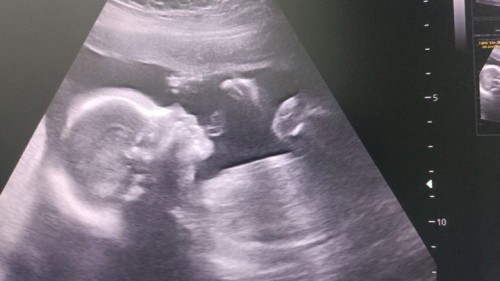

บ้านนี้ได้ลูกสาว 100% ค่า

ลูกคนแรกก็ลูกสาว คนนี้ก็ลูกสาวอีก 1 คน ตั้งครรภ์ได้ 21 สัปดาห์หมอบอกได้ลูกสาว 100% น้ำหนักแม่ไม่ขึ้นเลยค่ะ แต่เจ้าตัวเล็กน้ำหนักตามเกณฑ์ปกติทุกอย่างค่าา ตรวจน้ำตาลเรียบร้อย ค่าน้ำตาลปกติ 🥰